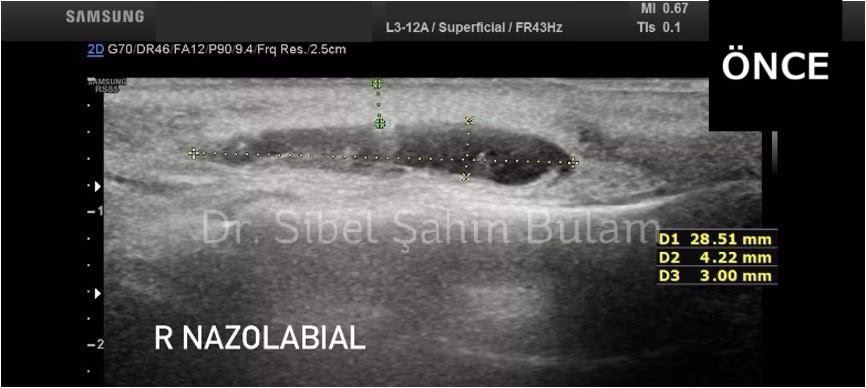

Örnek 1. Nazolabial Dolgu Ultrasonlu Eritme Öncesi ve 2. hafta kontrolü

Ultrason ile yapılan dolgu eritme işleminde, enzim enjeksiyonu, dolgunun konumunun ve derinliğinin canlı görüntüleme (real-time ultrasound) ile tespit edilmesiyle yapılır.

Muayene ve Görüntüleme: İlk olarak, dolgu bölgesi ultrason ile detaylı şekilde görüntülenir.